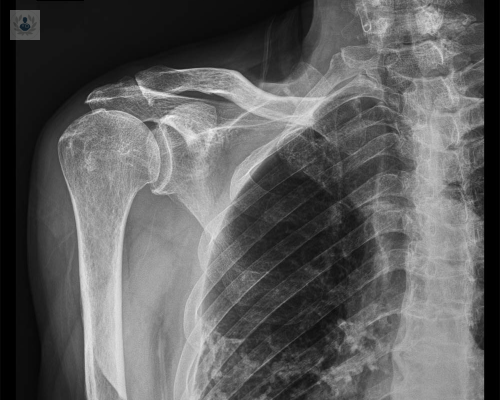

El manguito rotador del hombro es una estructura conformada por varios tendones ubicados en la parte superior del hombro. Esta estructura puede sufrir Lesiones debido a procesos degenerativos o traumáticos, generando dolor y limitaciones en la movilidad.

Una rotura puede ocurrir como consecuencia de un episodio traumático o desarrollarse gradualmente. Los pacientes cuyo inicio es gradual suelen tener síntomas previos de Tendinitis por Pinzamiento. La degeneración tendinosa ocasionada por la edad también provoca roturas.